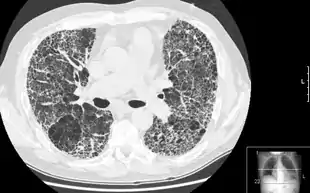

![]() HRCT of lung showing extensive fibrosis possibly from usual interstitial pneumonitis. There is also a large emphysematous bulla. | |

HRCT is used for diagnosis and assessment of interstitial lung disease, such as pulmonary fibrosis, and other generalized lung diseases such as emphysema and bronchiectasis.

HRCT may be diagnostic for conditions such as emphysema or bronchiectasis. While HRCT may be able to identify pulmonary fibrosis, it may not always be able to further categorize the fibrosis to a specific pathological type (e.g., non-specific interstitial pneumonitis or desquamative interstitial pneumonitis). The major exception is UIP, which has very characteristic features, and may be confidently diagnosed on HRCT alone.[6]